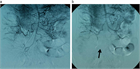

1. SMA閉塞症の疫学と初期診断:発症頻度は毎年5.6~8.6人/10万人と低いが、死亡率は24~94%と予後不良で、生命予後の改善には早期診断・治療が求められる(推奨度1J)

1. SMA閉塞症の画像診断による確定診断:問診・理学的所見・血液検査は必須であるが確定診断に至ることは困難であり、確定診断には画像評価が必須である(推奨度1J)